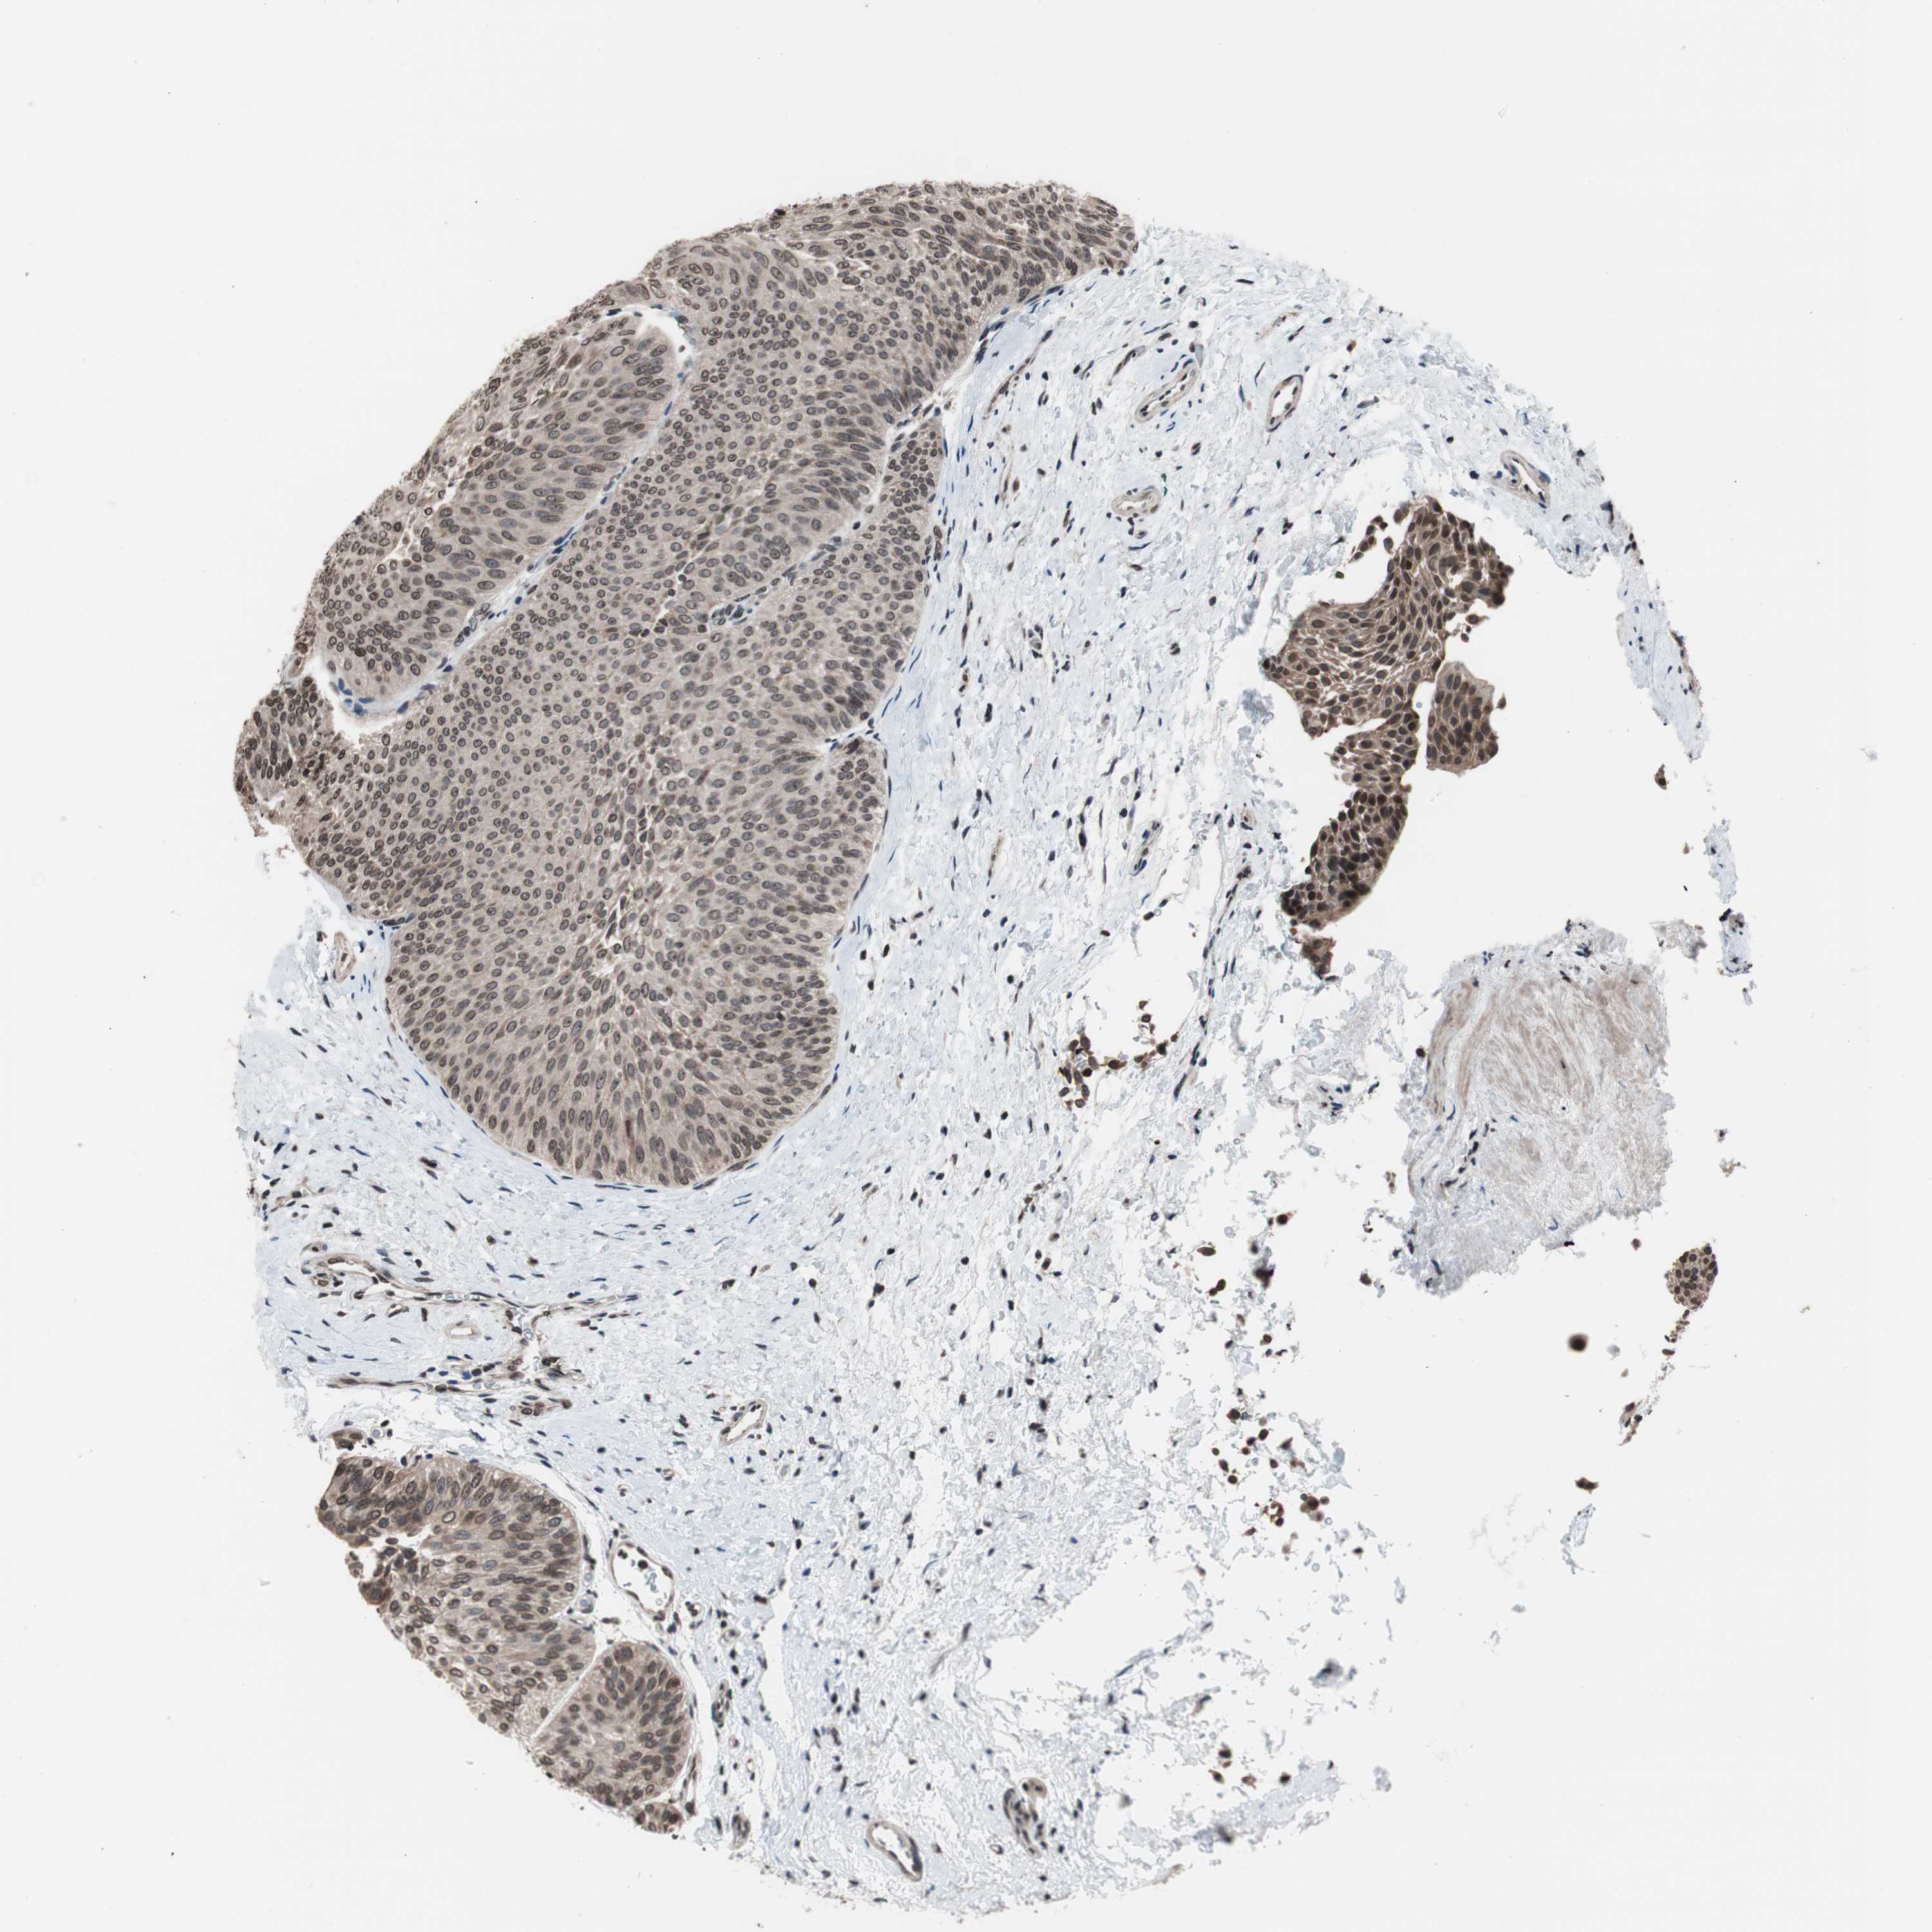

UROTHELIAL CANCER - Protein expressioni

A mouse-over function shows sample information and annotation data. Click on an image to view it in a full screen mode. Samples can be filtered based on level of antibody staining by selecting one or several of the following categories: high, medium, low and not detected. The assay and annotation is described here.

Note that samples used for immunohistochemistry by the Human Protein Atlas do not correspond to samples in the TCGA dataset.

Antibody stainingi

Antibody staining in the annotated cell types in the current human tissue is reported as not detected, low, medium, or high, based on conventional immunohistochemistry profiling in selected tissues. This score is based on the combination of the staining intensity and fraction of stained cells.

Each image is clickable and will lead to virtual microscopy that enables deeper exploration of all samples and also displays staining intensity scores, fraction scores and subcellular localization as well as patient and tissue information for each sample.

Antibody CAB009520

Staining

High

Medium

Low

Not detected

Intensity

Strong

Moderate

Weak

Negative

Quantity

>75%

75%-25%

<25%

None

Location

Nuclear

Cytoplasmic/membranous

Cytoplasmic/membranous,nuclear

Urothelial carcinoma, Low grade

Urothelial carcinoma, High grade